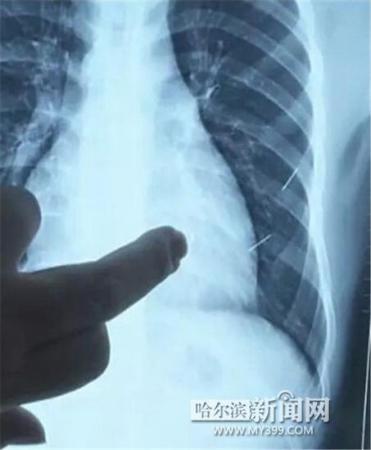

醫(yī)生指出X光片上的針狀物

昨日上午,記者在哈醫(yī)大二院第八住院部心外三病房找到了躺在病床上痛苦不堪的董立仁,家屬正在他身旁不斷安慰著他。見記者前來,董立仁母親李百燕拿出一張X光片,上面可以清晰地看到胸腔內(nèi)一共有4根針狀物,其中一根在心臟部位,兩根在胸腔壁上,還有一根在腹腔壁上。

心外三病房董立仁的主治醫(yī)生告訴記者,董立仁送到醫(yī)院時病情很危險,隨時可能危及生命?!巴ㄟ^檢查發(fā)現(xiàn),他心臟內(nèi)有一個金屬異物,正好在心臟上。心臟每次跳動都與其產(chǎn)生摩擦,導(dǎo)致出血,心包積液懷疑是血液。如果大量出血會凝結(jié)成血塊,血塊包裹住心臟就會影響心臟跳動,隨時都有停跳的危險。心臟上的異物是致命傷,其余胸腔壁和腹腔壁的異物傷害不大?!?/p>

隨后,在下胸壁位置,第二枚鋼針順利取出。在尋找另兩枚鋼針過程中,普外、胸外多名醫(yī)生也參與手術(shù),為主刀醫(yī)生提供更為穩(wěn)妥的處理建議。根據(jù)X光片顯示位置,醫(yī)生未在患者體內(nèi)找到剩余兩枚鋼針。醫(yī)生懷疑,其中一枚鋼針可能深藏在肋骨骨膜位置,無法尋找,最后決定結(jié)束手術(shù),做進一步觀察,研究下一次手術(shù)方案。